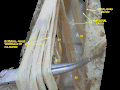

Filum terminal

Li, Lv. 1e et 5e vertèbres lombaires. SII 2è vertèbre sacrée. 1. Dure-mère. 2. Partie basse de la cavité subarachnoïdienne. 3. Extrémité basse de la moelle épinière. 4. Filum terminal interne. 5. Filum terminal externe.

6. Attachement du filum terminal au premier segment du coccyx.| Système | |